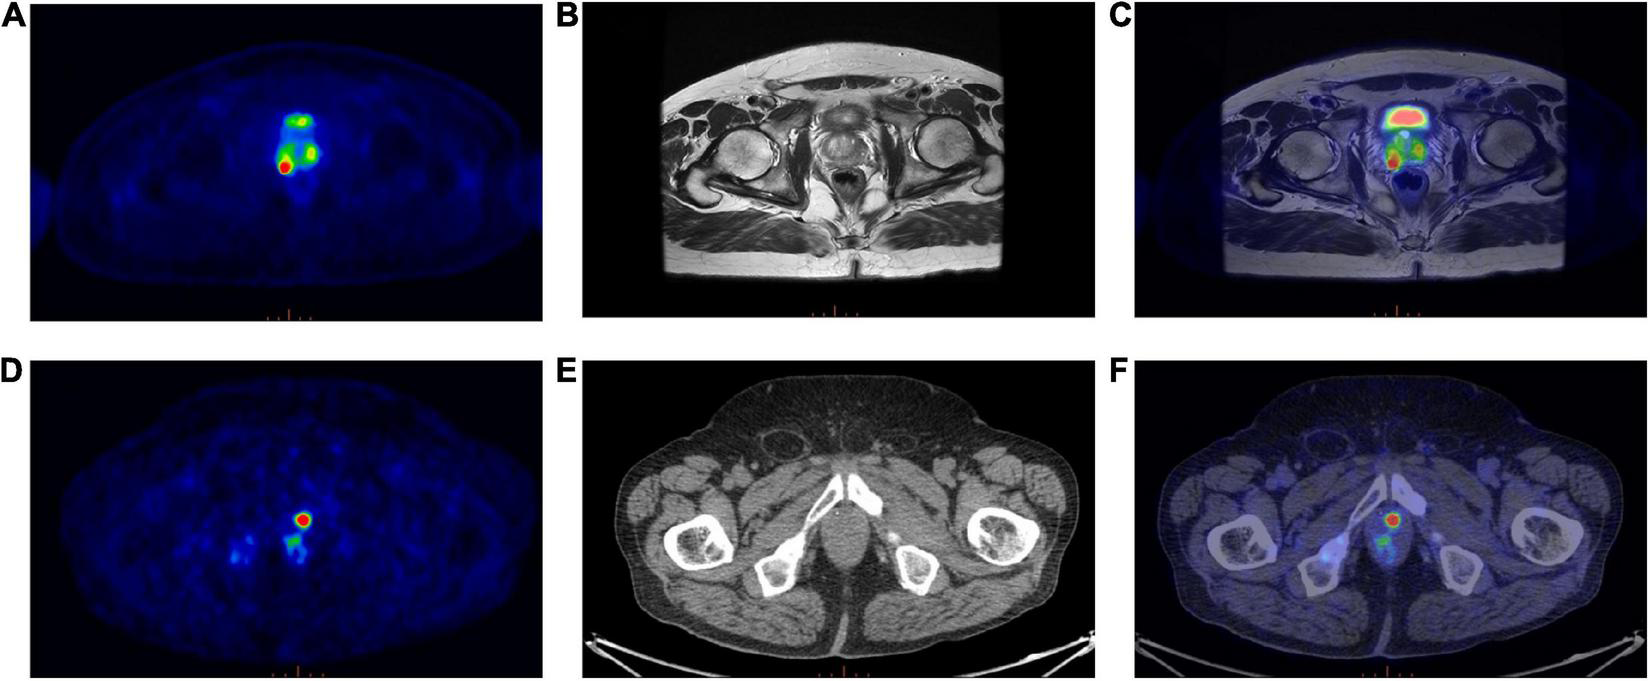

Eighty-five patients with biopsy proven PCa were enrolled in this study. The median age was 68 years (range: 45–85 years), whereas the median PSA level was 7.82 ng/ml. Patients’ characteristics are reported in Table 1. Forty-six out of 85 patients were examined on a PET/MRI scanner (see an example; Figure 2, top panel) and 39/85 on a PET/CT scanner (see an example; Figure 2, bottom panel).

FIGURE 2

(Top panel) Exemplar image of a 68Ga-PSMA PET/MRI scan; (A) Transaxial 68Ga-PSMA PET, (B) Axial T2-weighted MRI sequence, (C)68Ga-PSMA PET/MRI. (Bottom panel) Exemplar image of a 68Ga-PSMA PET/CT scan; (D) Transaxial 68Ga-PSMA PET, (E) Axial CT image, (F)68Ga-PSMA PET/CT.